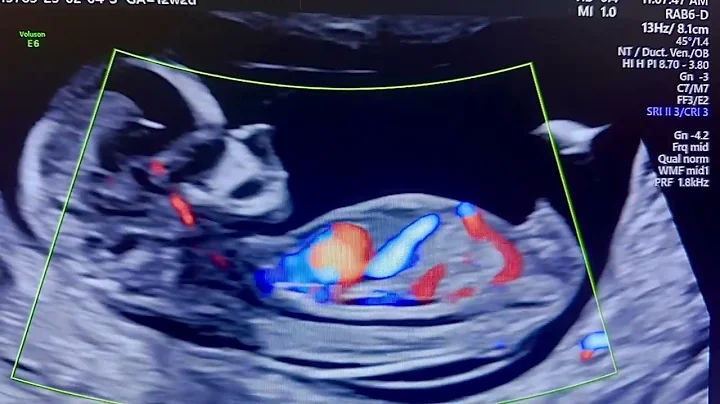

First Trimester Scan (6–12 Weeks) Explained | Dr. Siddhartha Sharma | Dg Diagnostics Paschim Vihar

Hello everyone! I'm Dr. Siddhartha Sharma, Consultant Radiologist at DG Diagnostics, Paschim Vihar. In today's video, we'll be ...